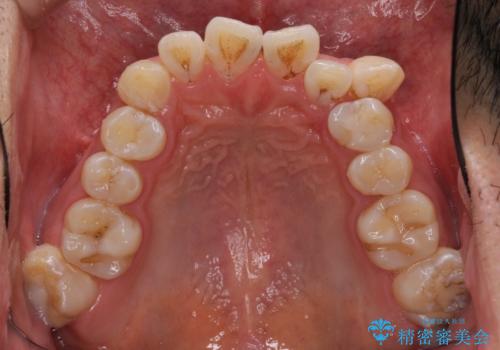

- 前歯の叢生と八重歯を気にして来院された患者様です。

叢生が強く、奥歯の咬合も左右差が大きかったため、上下左右4本を抜歯して、ワイヤー矯正を行うこととしました。